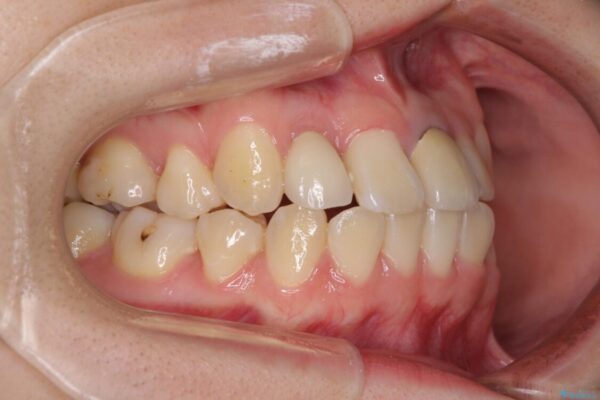

治療前

• 虫歯治療ついでに歯並びの後戻りを改善 インビザラインによる矯正治療 治療前画像